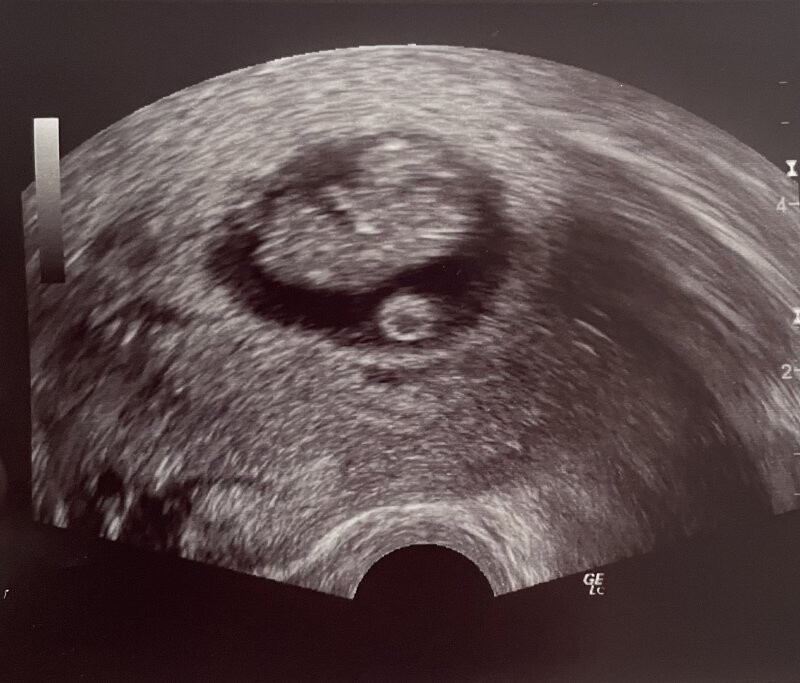

Dobrý den,mám dotaz, jestli můžete podle přiložené fotky z ultrazvuku posoudit velikost gestačního váčku vůči plodu? Bohužel nevím přesné rozměry, ale plod odpovídá přesně jak dle poslední MS má, hýbe se a má srdeční činnost, na UTZ těhotenství 9+3. Lékař mi nic špatného ohledně velikosti gestačního váčku neříkal. Pouze já až doma, jak koukám na fotku, tak si říkám, jestli tam má dostatek prostoru. Ve chvíli kdy mi byl UTZ prováděn mě to vůbec nenapadlo. Děkuji za Vaši odpověď.

pokud Váš lékař na ultrazvuku nic podezřelého neshledal, tak se nyní nemáte důvod obávat. Já se z pozice internetové poradny k cizímu ultrazvuku vyjadřovat nemohu, popisovat takto od počítače, bez možnosti si ultrazvuk provést osobně, je prakticky nemožné.